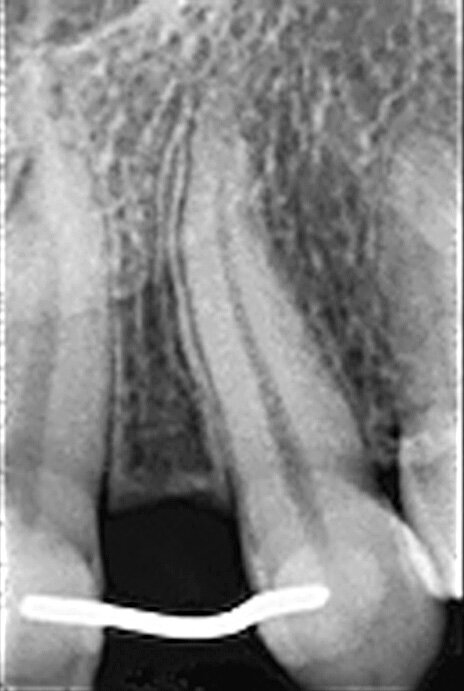

Fig. 8 : Radiographie de contrôle finale trois ans après la mise en fonction. Il faut noter le design de platform-switching entre le col de l’implant et la base hémisphérique du pilier.

L’implant a été mis en place au moyen d’un instrument spécial pour l’insertion d’implant, qui permet au praticien de pousser l’implant fermement, en appliquant une pression précise dans l’ostéotomie (Fig. 5). La dernière étape a consisté à introduire complètement l’implant au moyen du maillet, et de l’instrument d’insertion fixé à la poignée de serrage droite. L’implant étroit était dès lors bien positionné entre les deux racines (Fig. 6). L’implant de 8 mm de long et de Ø 3 mm a été inséré par l’application d’une pression dans l’ostéotomie, et l’utilisation du maillet et de l’instrument d’insertion à 3 mm sous le niveau de l’os crestal (Fig. 7). La seconde phase du traitement a été réalisée après six mois de cicatrisation et a consisté à désenfouir l’implant. Un pilier ayant un corps de Ø 2 mm et une base hémisphérique de Ø 4 mm a été choisi pour connecter les couronnes provisoires à l’implant. Il est important de veiller à la bonne cicatrisation du tissu mou autour du contour coronaire adéquat, et celle-ci peut être obtenue par une modification du profil d’émergence de la couronne provisoire jusqu’à la formation des papilles. Après la cicatrisation complète du tissu mou, la dernière empreinte a été prise et la couronne définitive a été scellée sur le pilier en titane (Figs. 8 et 9).